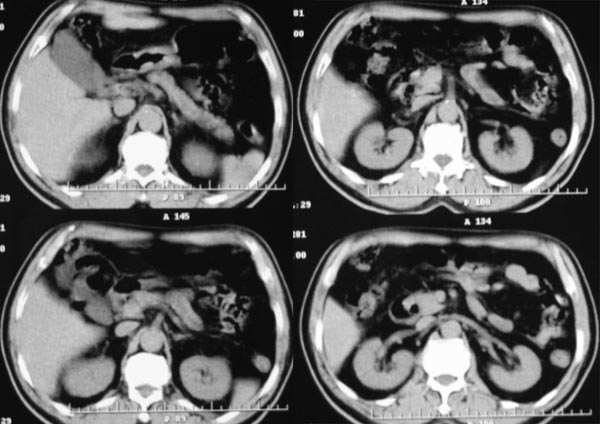

患者,m,71y,乏力、纳差、巩膜黄染两月余,b超示肝内占位性病变。

平扫

动脉期

门脉期

延时期

2.病灶特点:平扫呈低密度,密度不均,中央呈更低密度;动脉期病灶周围强化较明显,高于正常肝组织,低于同层主动脉密度,中央坏死区未见明显强化;门静脉期,病灶呈低密度,低于正常肝组织密度。

病灶特点:1、平扫:肝右叶大片状低密度影,内见更低密度影,边界不清

2、动脉期:病灶边缘强化明显,明显高于肝实质,中间未强化为坏死区

3、门脉期:病灶呈低密度,低于肝实质,下腔静脉见充盈缺损,说明癌栓形成

综上所述,符合肝癌伴下腔静脉癌栓形成